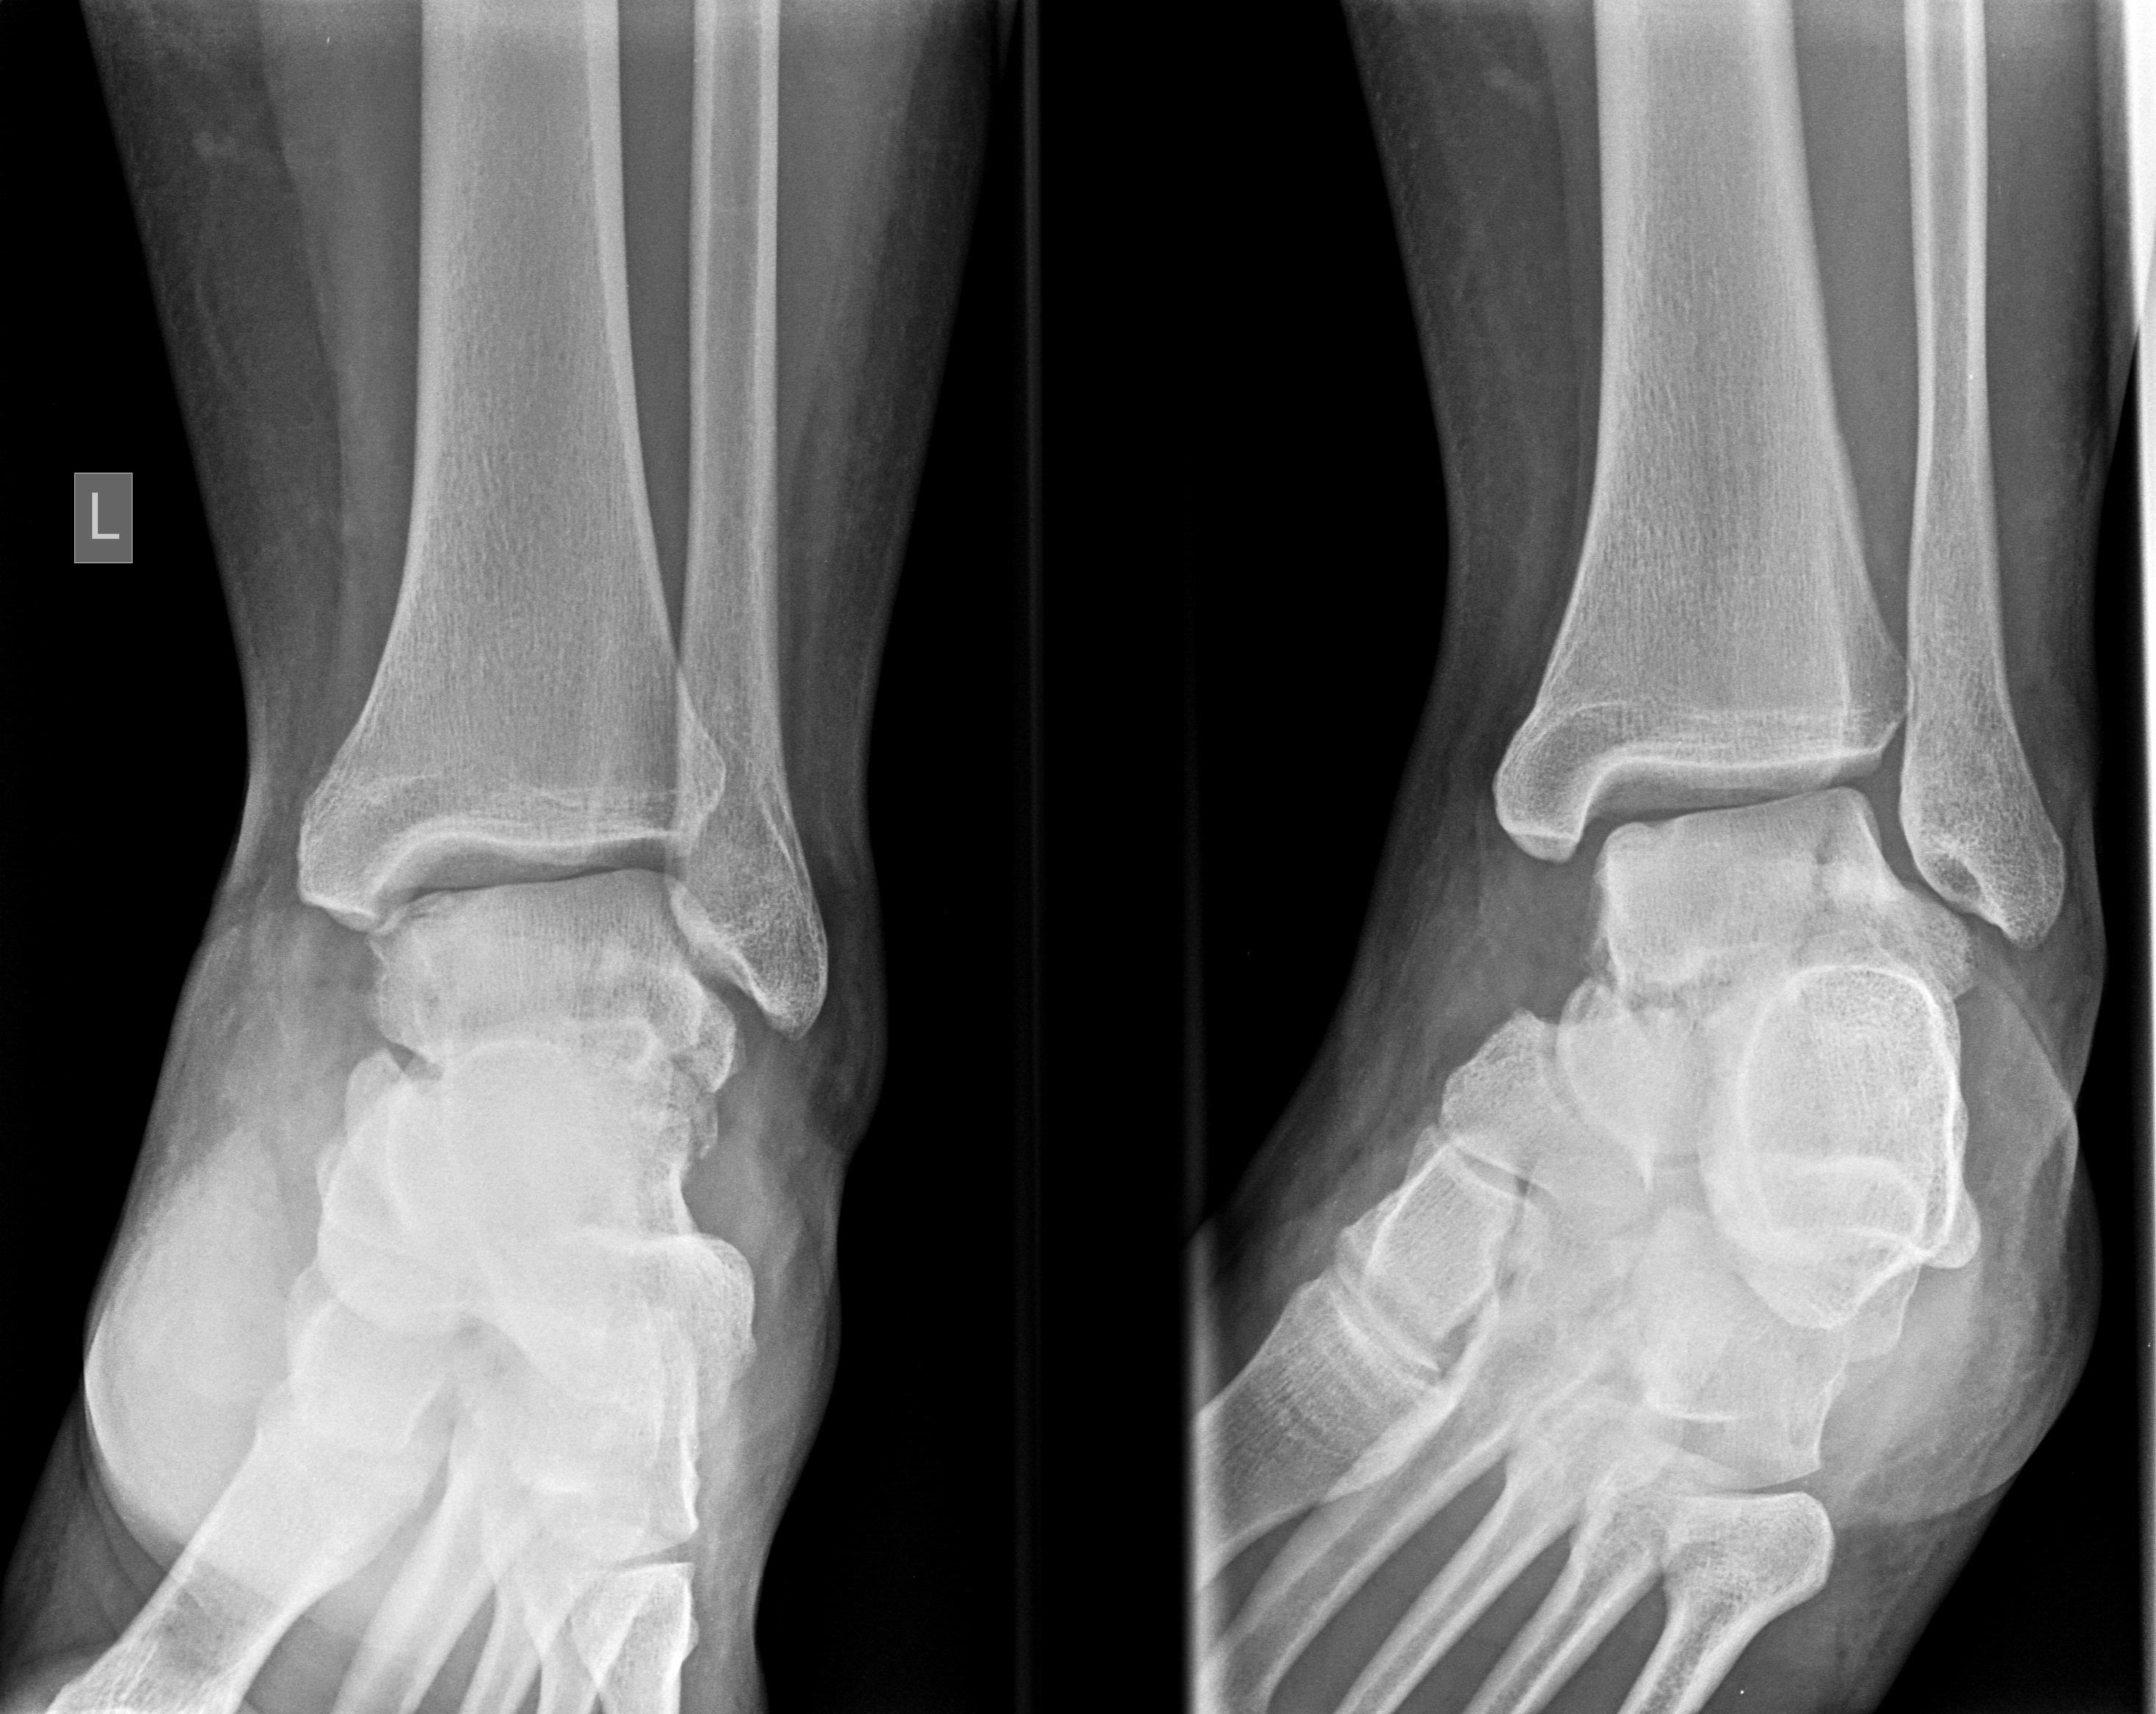

Anteroposterior, mortise and true lateral views of the left foot and ankle radiographs were obtained (Figure 1 and Figure 2). A displaced lateral talar body fracture and subtalar joint disruption, as well as a tilt of the tibiotalar joint, were revealed from the plain radiographs. Osteochondral defect on the medial side of the dome of the talus, due to an old ankle injury, sustained few years ago, was also visible. CT scan of the left foot confirmed a displaced lateral talar body fracture along with a displaced sustentaculum tali fracture (Figure 3, Figure 4 and Figure 5).

Figure 1: Ankle AP and mortise view. Lateral talar body fracture is noticed. View Figure 1

Figure 2: Foot and Ankle true lateral view. Sustentaculum tali fracture and subtalar disruption due to talar body fracture is identified. View Figure 2